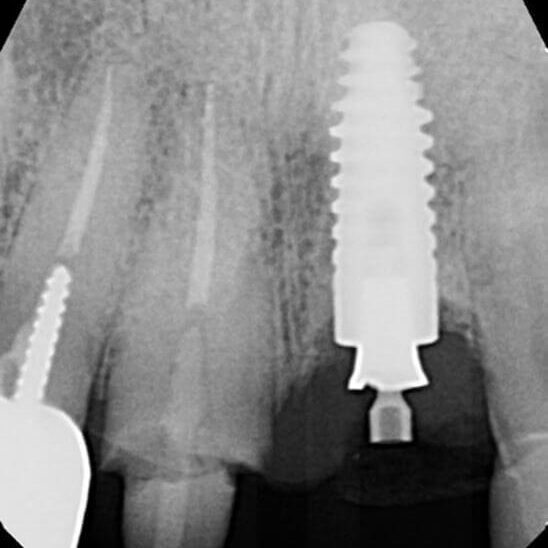

ULTRASONICS: Complications of Abutment Screw Retrieval Secondary to Prior Ultrasonic Attempts

There has been much written on the use of ultrasonics in retrieving fractured screw fragments, which I didn’t think a lot about until May of 2023, as it has not been a part of my fractured screw retrieval algorithm.